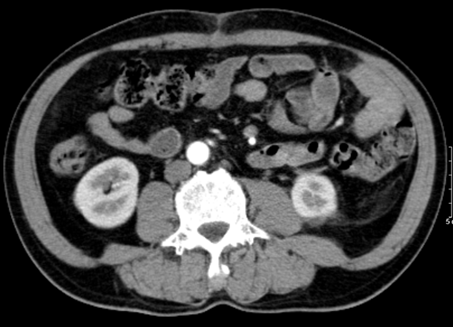

- Chụp cắt lớp vi tính ổ bụng: Vùng mạn sườn trái có tổn thương kích thước ~ 108x114x130mm, tỷ trọng hỗn hợp gồm phần dịch trung tâm và phần đặc, kèm vài nốt vôi hóa rải rác, phần đặc ngấm thuốc không đồng nhất sau tiêm, thâm nhiễm xung quanh. Tổn thương đè đẩy thận trái lên trên, vào trong, có phần ranh giới không rõ với thận trái.

Hình 1: Hình ảnh chụp cắt lớp vi tính bụng: u vùng mạn sườn trái có tổn thương tỷ trọng hỗn hợp kèm vài nốt vôi hóa rải rác, thâm nhiễm xung quanh (mũi tên vàng).